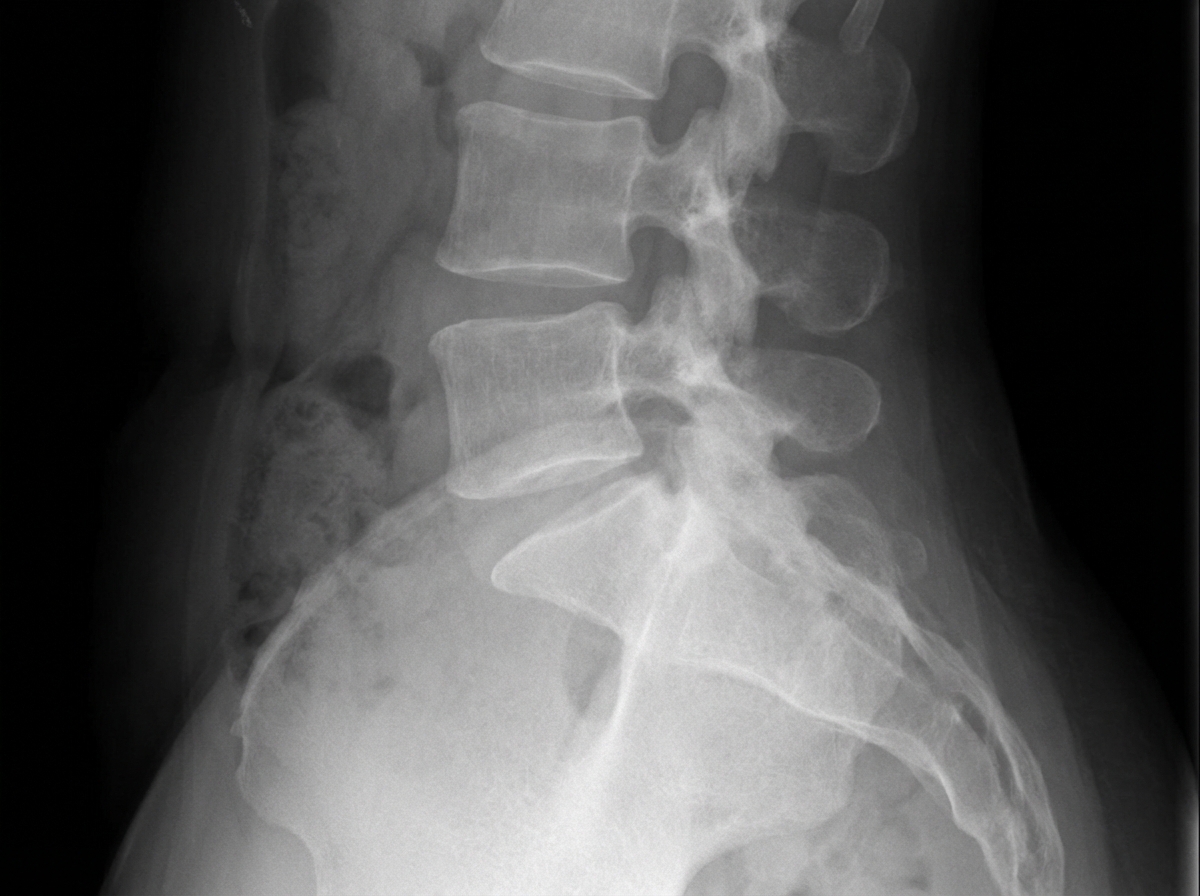

A lateral view X-ray of the lumbosacral spine shows which of the following findings?

Explanation: ***Spondylolisthesis*** - **Lateral X-ray** is the gold standard for diagnosing spondylolisthesis, showing **anterior slippage** of one vertebra over another with a characteristic **step-off deformity**. - The **Meyerding classification** can be applied on lateral views to grade the degree of vertebral displacement. *Pott's spine* - Shows **vertebral body destruction** and **collapse** with **kyphotic angulation** rather than forward slippage. - Associated with **paravertebral soft tissue shadows** and **cold abscesses** due to **tuberculosis**. *Spondylosis* - Demonstrates **degenerative changes** like **osteophyte formation** and **disc space narrowing** without vertebral displacement. - Shows **facet joint arthritis** and **sclerosis** but lacks the **step-off deformity** seen in spondylolisthesis. *Ankylosing spondylitis* - Presents with **bamboo spine** appearance due to **syndesmophyte formation** and **vertebral fusion**. - Shows **sacroiliac joint erosion** and **squaring of vertebral bodies**, not vertebral slippage.